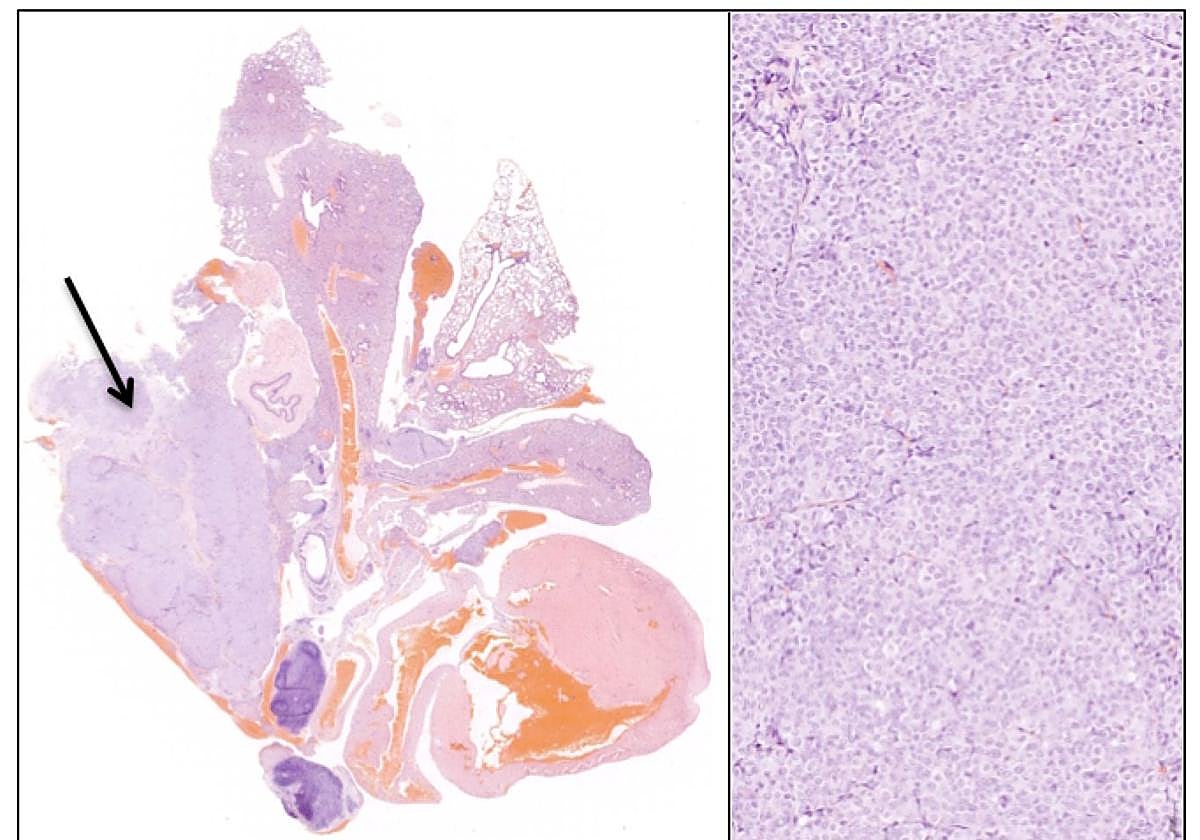

En paralelo, este equipo ha abordado la misma problemática en tumores BRAF V600E cuyo tratamiento actual consiste en una combinación de dos fármacos. Al estar presente en una menor proporción de pacientes (alrededor de un 4% de todos los adenocarcinomas pulmonares son causados por BRAF V600E) el conocimiento actual de los mecanismos que inducen resistencia al tratamiento es mucho menor. En este trabajo, mediante estudios genéticos y bioquímicos, los investigadores han identificado que, en las etapas iniciales de la resistencia al tratamiento, los tumores BRAF V600E sufren un elevado estrés oxidativo que es en gran medida aliviado por la actividad de una enzima con actividad peroxidasa denominada GPX4.

En consecuencia, mediante el empleo de modelos animales el estudio demuestra que fármacos inhibidores de GPX4 elevan el estrés oxidativo hasta umbrales letales que impiden la progresión tumoral y retardan, en gran medida, la evolución de los tumores resistentes. Lamentablemente, a diferencia de KRAS G12C, no existen actualmente fármacos contra GPX4 lo suficientemente avanzados como para permitir su uso en pacientes. Este estudio, por tanto, ha identificado y validado una posible diana terapéutica que necesitará del desarrollo a futuro de una nueva generación de inhibidores.